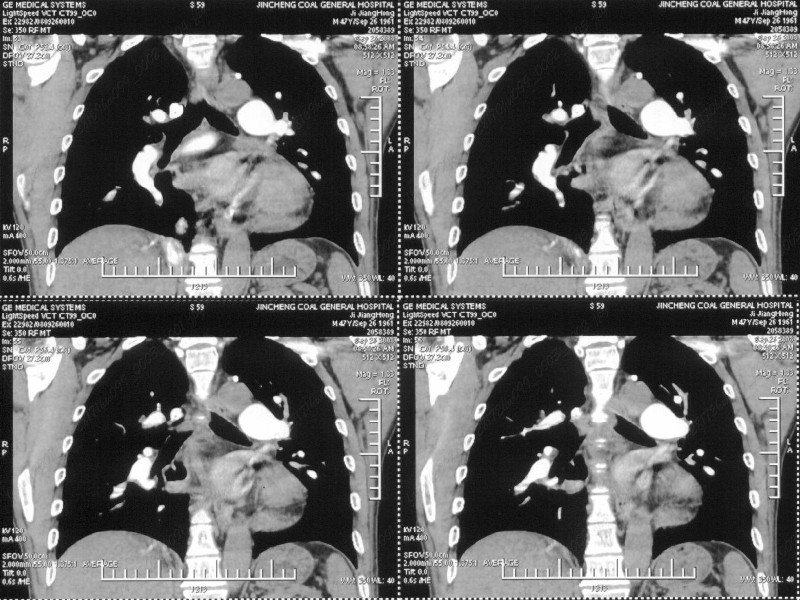

男性,47岁。胸部不适一年,ct检查发现右胸膜下结节。http://www.radida.com/bbs/forum.php?mod=viewthread&tid=46094

图像很清,资料很全。工作做的很细,向您学习!观阁下的强化图像发现,您们强化后扫描时间挺早,延迟时间大约在16—18秒之间吧。估计目的是为了观察肺动脉及分支的情况。但现有的资料并不能提示动脉栓塞改变。建议楼主可在机器上仔细观察,或许会有异常发现。另外,个人感觉右侧应为肺内结节而非胸膜结节。考虑肺内良性小结节,炎性假瘤可能性大。

病灶周围似有纤维化征像,增强明显强化,但中央可见点状低强化区,考虑慢性病变可能如炎性假瘤等,病灶边缘部分毛糙有切迹,双侧胸腔少量积液影,不除外恶性

结节未见明显强化,局部胸膜增后粘连,内缘纹理影增重伴小围星灶,局部胸膜下小三角状实变影,尖端见纤维索牵扯征,综合考虑炎性病变,有增殖表现,不出外tb灶

汇报临床诊断:右肺动脉分枝栓塞

右肺静脉充盈缺损,左心房体积小,右肺动脉远端动脉充盈缺损,右肺血管影细小,考虑;右肺动脉远端栓塞.